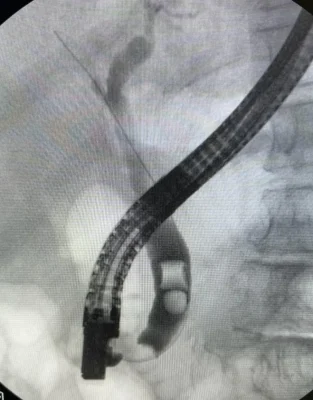

Colangioresonancia: este estudio permite evaluar la presencia de Cálculos en las vías biliares, esta condición corresponde a una enfermedad más compleja y requiere el drenaje de cálculos de la vía biliar adicionalmente a la Colecistectomía.